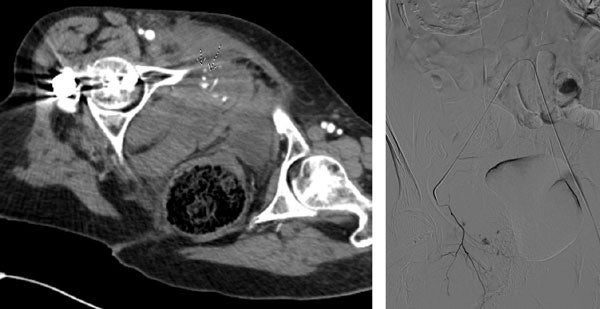

The patient’s BP stabilized in the room immediately post embolization. Post-op there were no additional signs of bleeding with stable hgb and vitals. Follow up CTA was performed 2 days post embolization with no further sign of extravasation or pseudoaneurysm. The cast of Obsidio Embolic is noted in the follow up CTA (CT image 2, arrows). The patient was discharged to a SNF 4 days post intervention.

Scan images from Obsidio case.